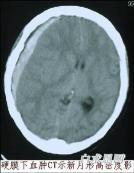

• 慢性硬腦膜下血腫

慢性硬腦膜下血腫系外傷后3周以后出現(xiàn)癥狀,位于硬腦膜與蛛網(wǎng)膜之間,具有包膜的血腫。多數(shù)頭部外傷輕微,部分外傷史缺乏,起病緩慢,無(wú)特征性臨床表現(xiàn),早期臨床表現(xiàn)癥狀...